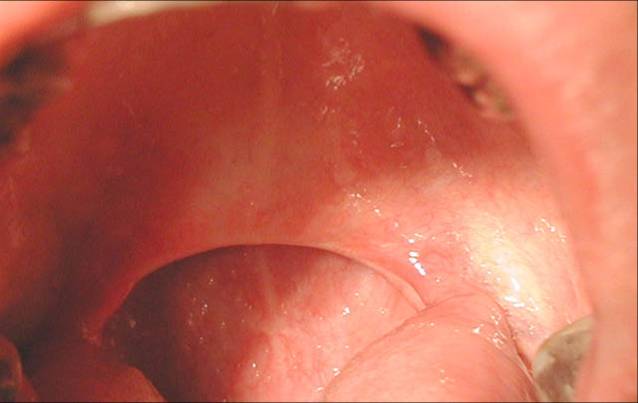

| Local finding in the throat that represents optimal conditions for arco-palato-uvular flap application Rear palate arches are wide and, rugged, palate thinned, downcast, uvula short, tonsils earlier excluded |

Local finding in the throat that represents optimal conditions for arco-palato-uvular flap application Rear palate arches are wide and, rugged, palate thinned, downcast, uvula short, tonsils earlier excluded Criteria for surgical treatment (Dr. Vukoje Method):